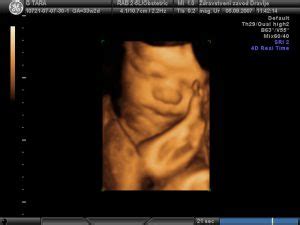

Če nosečnica kadi, strupene snovi iz tobačnega dima preko njenega krvnega obtoka dosežejo tudi še nerojenega otroka. Kajenje nosečnice povzroča upočasnjeno rast še nerojenega otroka in manjšo porodno težo. Nikotin in ogljikov monoksid vplivata na oskrbo ploda s kisikom. Poleg tega nikotin prehaja skozi posteljico in doseže višje koncentracije v plodu kot v materi. Nikotin se koncentrira v krvi ploda, amniotski tekočini in materinem mleku, kar plod in dojenčka izpostavlja tveganju. Kajenje lahko povzroči tudi predležečo posteljico ali prezgodnjo ločitev posteljice, prezgodnji porod in zmanjšanje pljučne funkcije pri otroku. Obstajajo tudi dokazi, ki povezujejo kajenje matere z večjo pojavnostjo zunajmaternične nosečnosti in spontanega splava.

Škodljivi vplivi tobaka med nosečnostjo s svojimi škodljivimi posledicami lahko vplivajo na vsa trimesečja nosečnosti. V prvih treh mesecih nosečnosti, ko pri plodu poteka izoblikovanje in razvijanje organov, so učinki kajenja tobaka najbolj vidni. Organi so lahko manjši, občutljivejši, v ekstremnih primerih pa se pojavijo hude anomalije in deformacije ploda. Kadilke imajo tudi višje tveganje za izvenmaternično nosečnost in nepravilnosti posteljice.